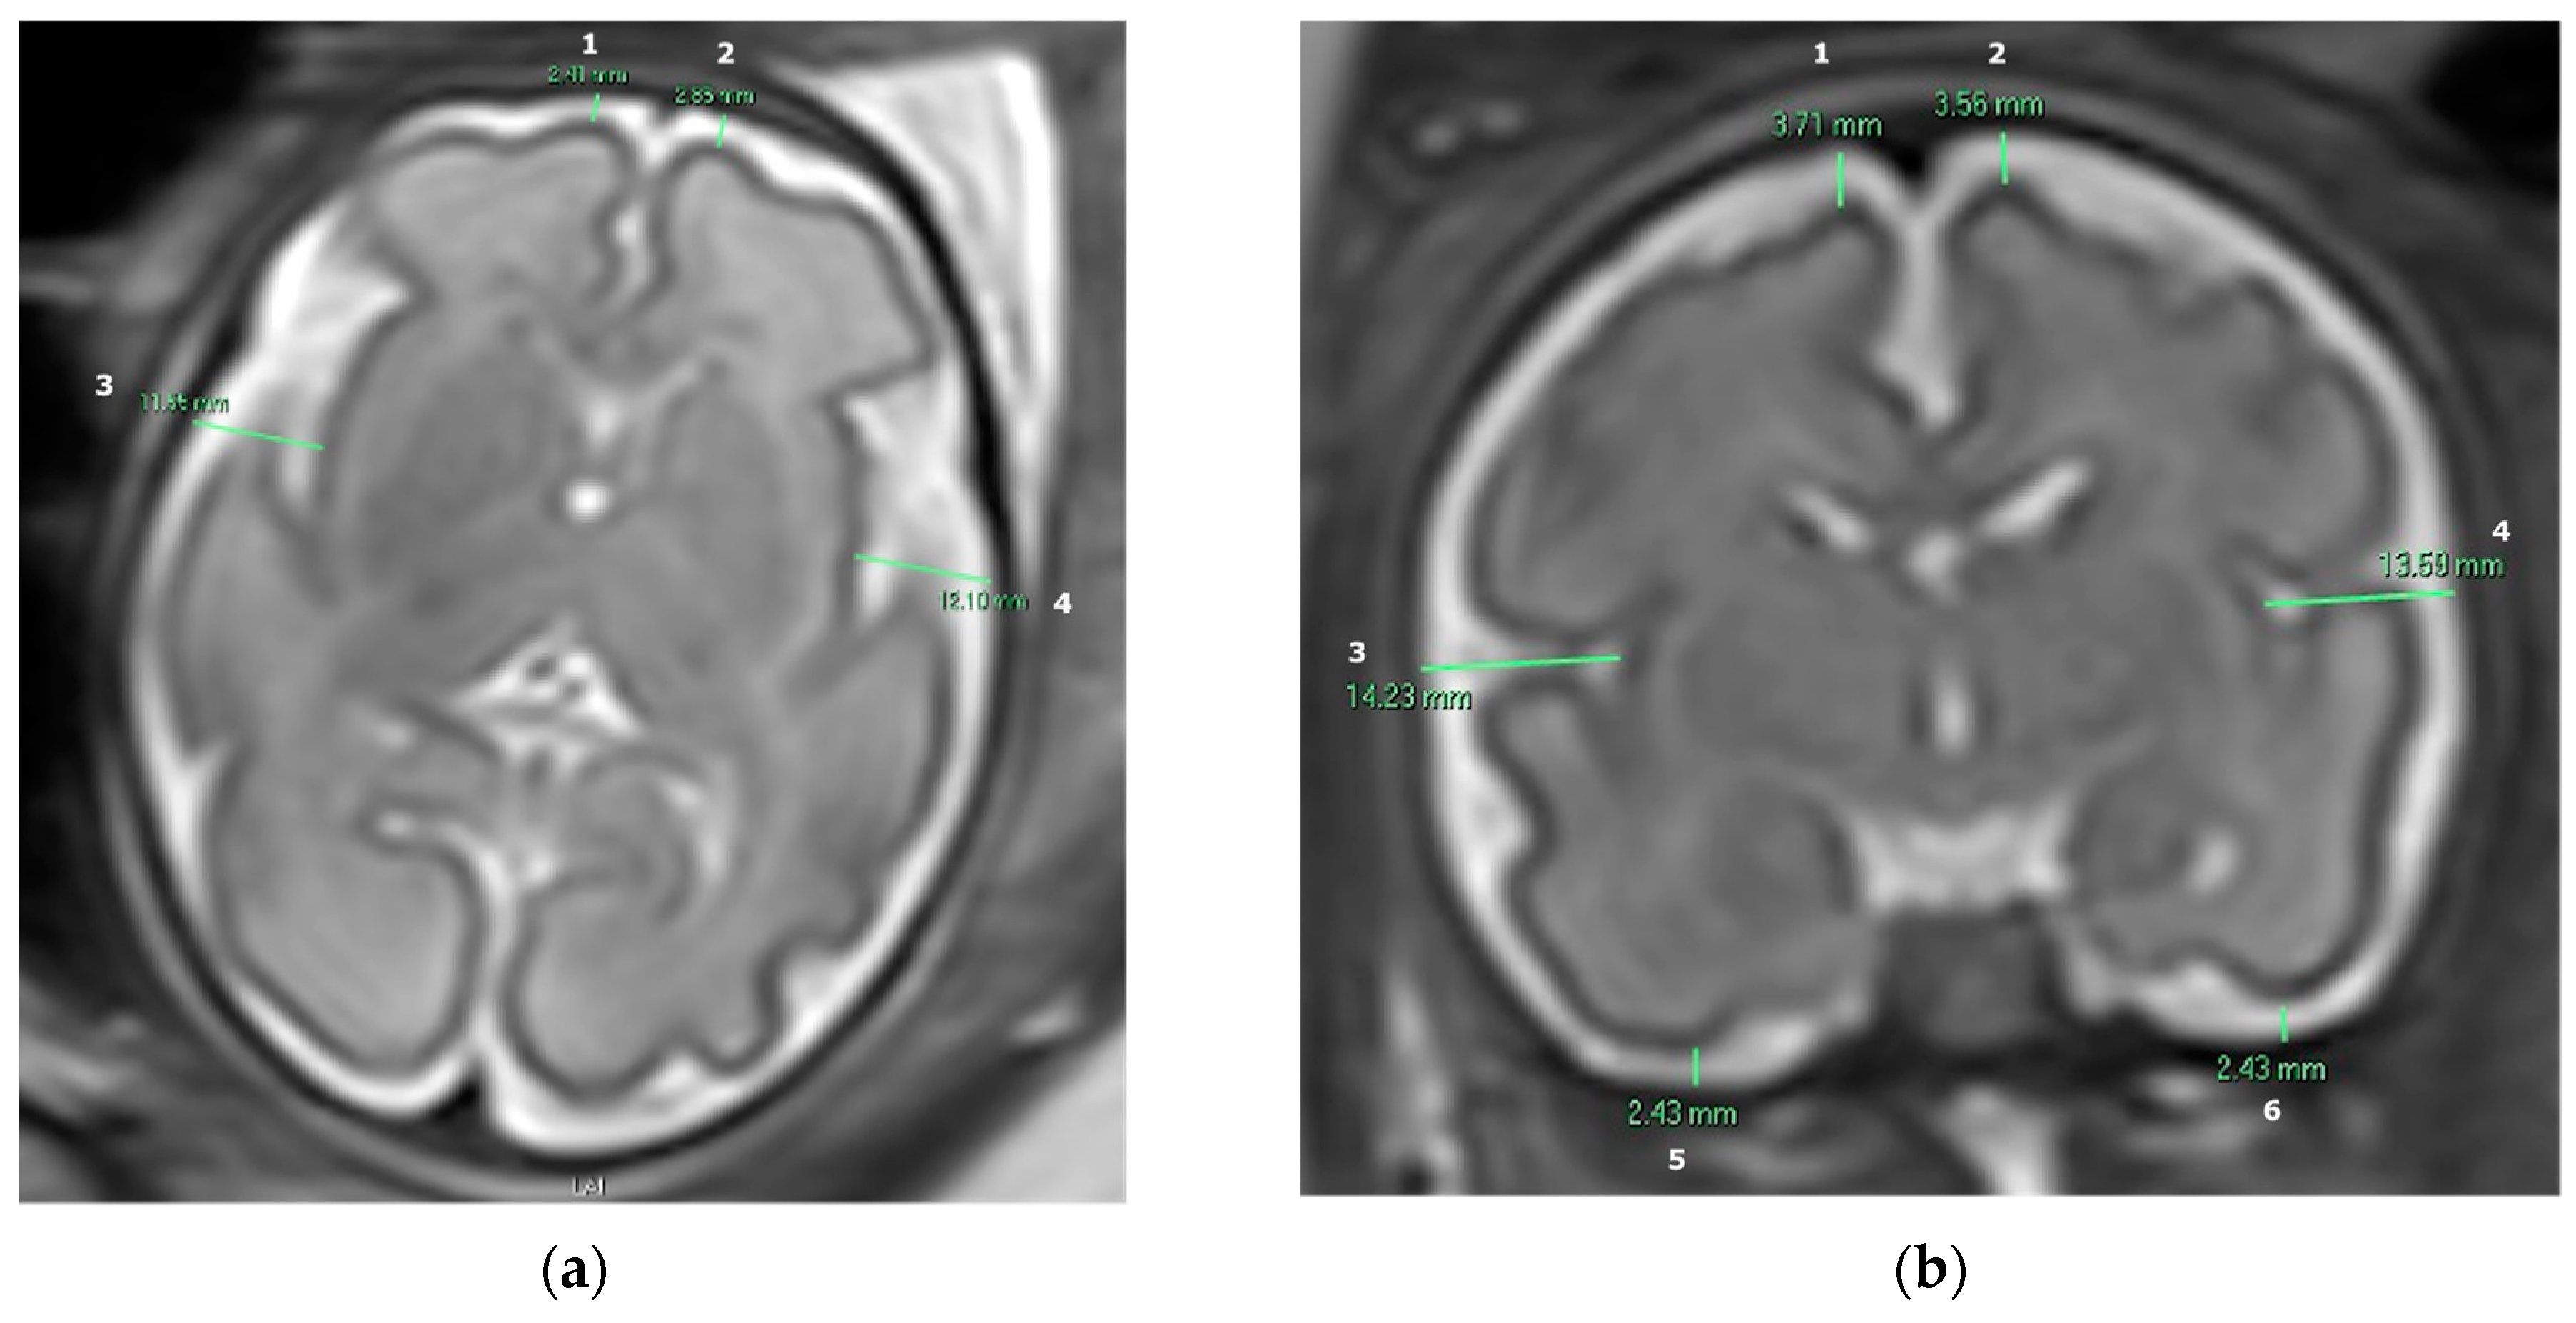

The subarachnoid space width was measured in MR images in both axial and coronal planes in ten specific anatomical locations. Measurements were conducted manually in 2D slices using the Carestream Vue PACS system, width measured in millimeters. We obtained four measurements in the axial plane: the right and left frontal gyri and the right and left insula gyri. We also obtained six measurements in the coronal plane: the right and left frontal gyri, the right and left insula gyri, and the right and left inferior temporal gyri, as presented by Figure 1.

Figure 1.

T2-weighted fetal brain MR image demonstrating the measurements of the subarachnoid space in millimeters: (a) Axial plane: (1) Right frontal gyrus. (2) Left frontal gyrus. (3) Right insula gyrus. (4) Left insula gyrus. (b) Coronal plane: (1) Right frontal gyrus. (2) Left frontal gyrus. (3) Right insula gyrus. (4) Left insula gyrus. (5) Right inferior temporal gyrus. (6) Left inferior temporal gyrus.